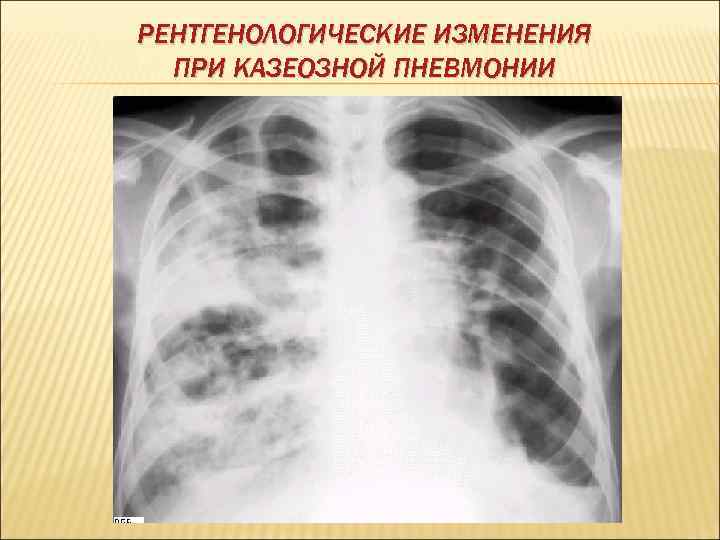

КАЗЕОЗНАЯ ПНЕВМОНИЯ Острая специфическая пневмония, которая характеризуется быстро нарастающими казеозно-некротическими изменениями и тяжелым, нередко быстро прогрессирующим течением и высокой летальностью. Патогенез и патоморфология: Возникновению казеозной пневмонии способствует резкое истощение защитных сил организма массивная вирулентная инфекция. Казеозная пневмония может осложнять течение фиброзно- кавернозного, диссеминированного, инфильтративного, а так же первичные формы туберкулеза. В зависимости от патоморфологических изменений выделяют ацинозную, лобулярную и лобарную казеозную пневмонию.

РЕНТГЕНОЛОГИЧЕСКИЕ ИЗМЕНЕНИЯ ПРИ КАЗЕОЗНОЙ ПНЕВМОНИИ

КЛИНИКА КАЗЕОЗНОЙ ПНЕВМОНИИ острое начало с высокой температурой тела, тяжелые симптомы интоксикации одышка боль в грудной клетке, кашель с выделением мокроты, содержащей примеси крови. перкуторно определяется тупой звук аускультативно – большое количество звучных разнокалиберных, иногда хлюпающих, влажных хрипов МБТ в мокроте определяются в случае образования полостей распада при исследовании крови – лейкоцитоз (14 -20 х109/л), сдвиг лейкоцитарной формулы влево, повышение СОЭ до 50 -70 мм/ч рентгенологически определяется массивное затенение без четких границ, первоначально гомогенного характера, позже – с наличием полости распада.